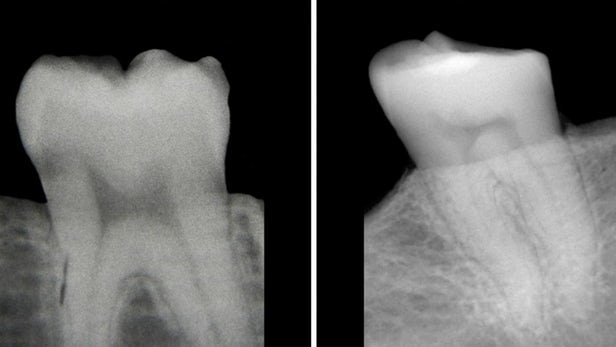

آنها دریافتند که پاسخ در شکل پالپ دندان قرار دارد که سایه تاریک در وسط یک تصویر رادیولوژی دندان است.

در یک فرد سالم، این قسمت دندان به شکل یک قوس بالای دو شاخ است. با این حال، در افرادی که دچار کمبود ویتامین D هستند، شکل پالپ نامتقارن و سفت و سخت است.